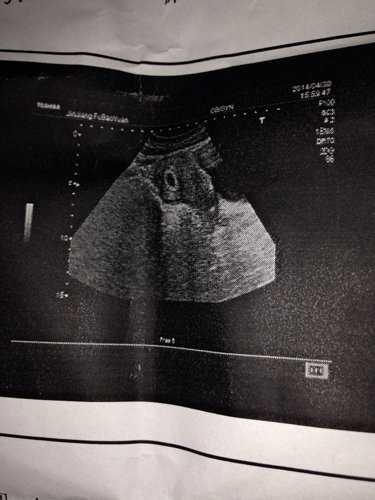

B超检查宫体大小67.48.57mm.宫内见一妊娠囊回声,大小15X9X10mm内可见卵黄囊,未见胚芽及胎心管搏动,双卵巢大小正常,超声孕龄如5+周,未见胎心管搏动,我上个月21号来姨妈27号走的这个月超了十天没来姨妈,请问我怀孕多久了,这个B超检查正常吗

病情分析: 您现在彩超检查的结果和您停经鱼粉是相符合的,不用担心,及时观察看 指导意见: 必要的情况下需哟啊及时抽血化验HCG和孕酮检查,及时根据检查的情况对症治疗